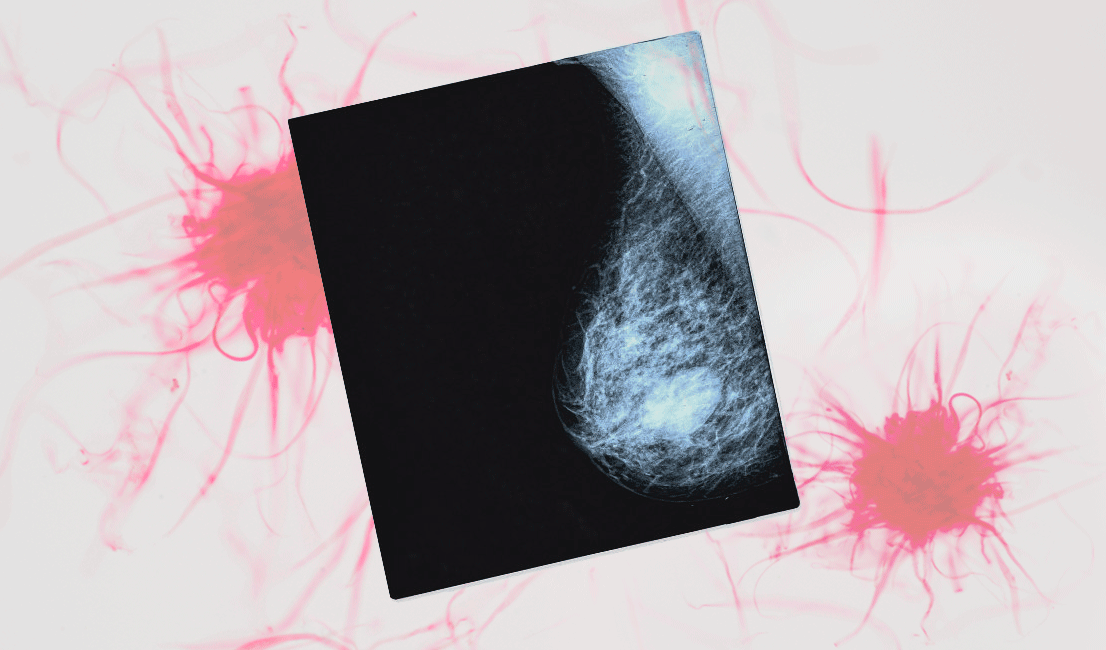

Хотя заболевание чаще всего обнаруживают у женщин от 45 до 65 лет — на них приходится больше половины случаев — это не означает, что онкология не касается молодых девушек. На ранней стадии болезнь можно обнаружить при помощи маммографии — рентгеновского снимка молочной железы. Подобная процедура обязательна для всех женщин старше 50 лет, однако ты можешь пройти ее раньше — по собственному желанию или по назначению врача.